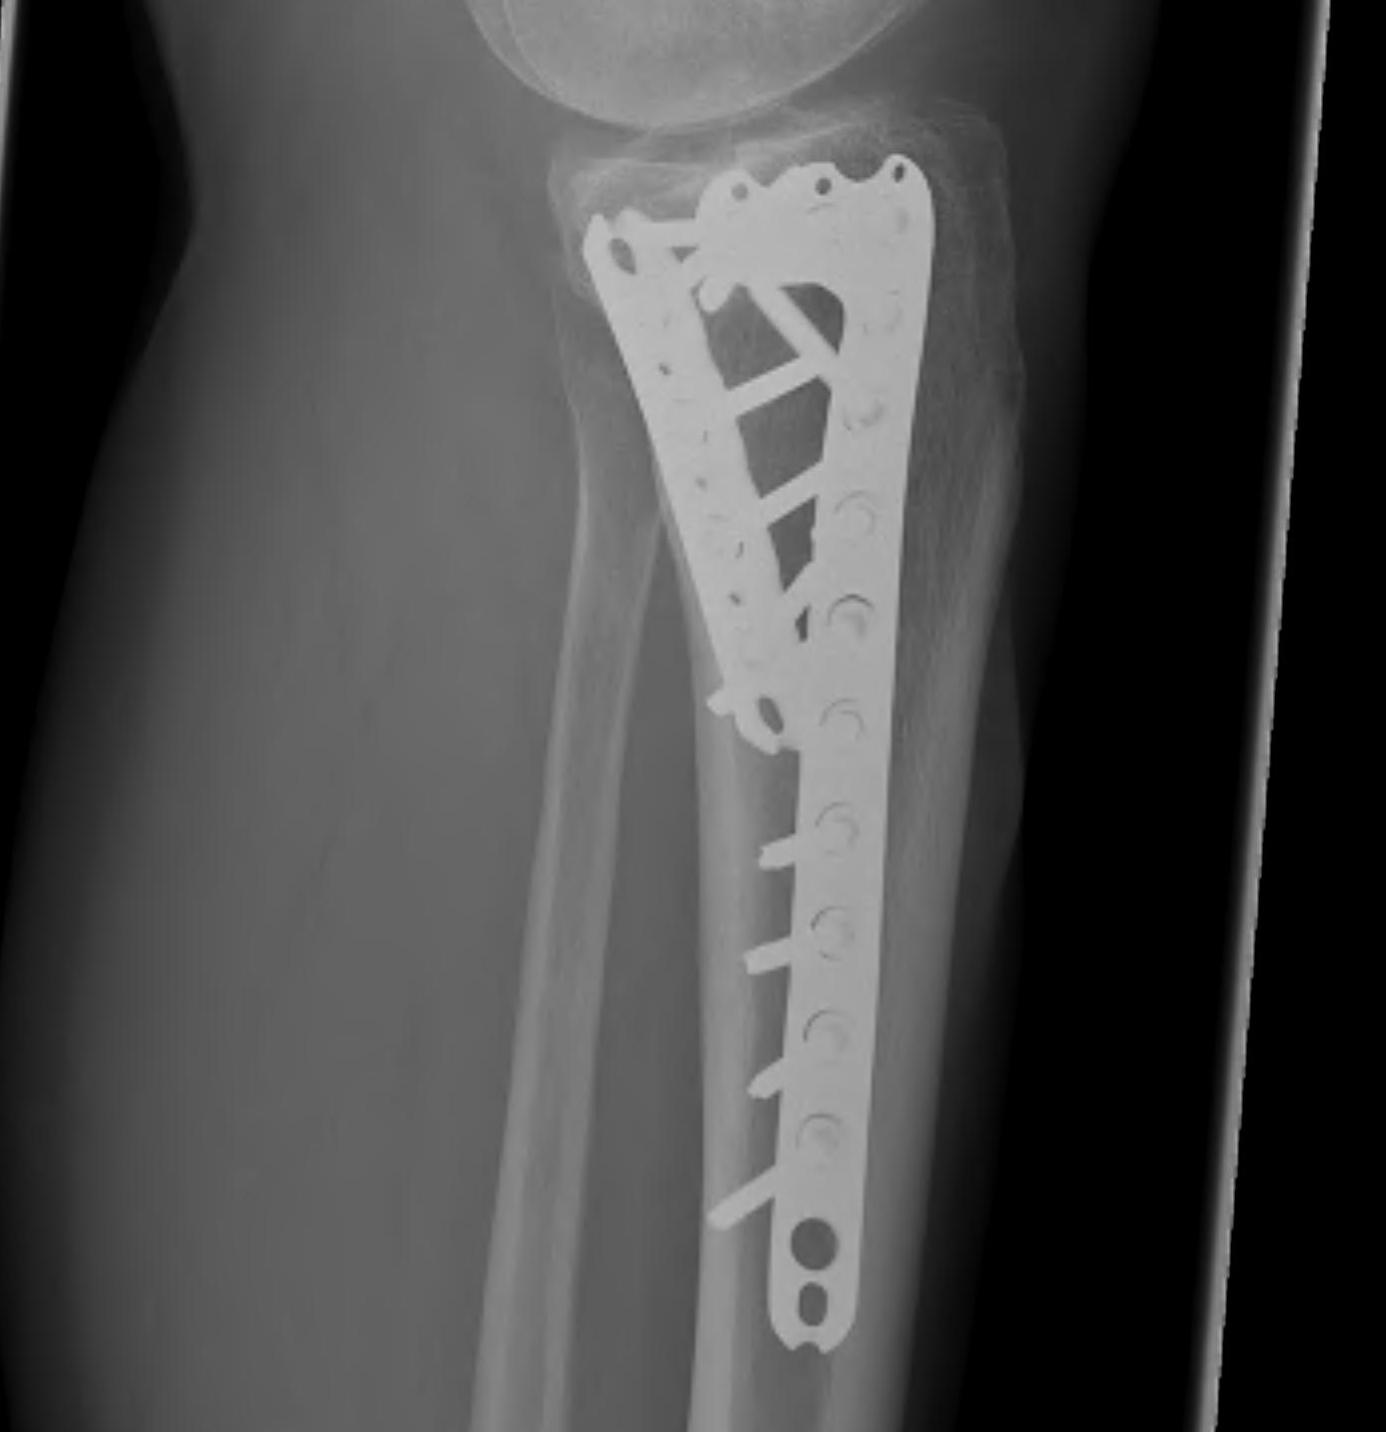

1. Medial and Lateral Plating

Technique

- depends on which of the three columns affected

- anterolateral approach for lateral column

- posteromedial appraoch for medial / posterior column